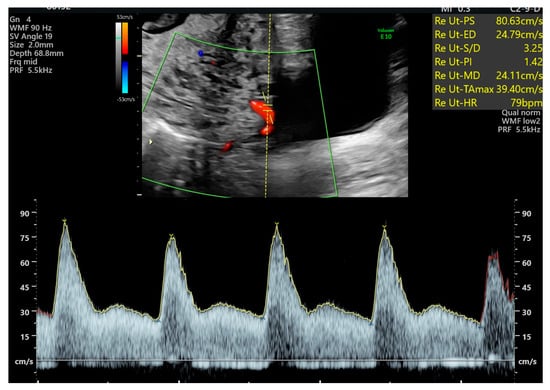

The Due date was calculated based on the first day of the last menstrual period and adjusted to ultrasound findings. Ultrasound examinations were performed using either a Toshiba Xario, a Toshiba Aplio (Canon Medical System Ltd., Ōtawara, Japan), as well as a Voluson E8 Expert system equipped with a transabdominal RAB 4-8-D convex probe or a GE Healthcare Voluson E10 system (GE HealthCare, Zipf, Austria) with a transabdominal RM6C convex probe. Chorionicity was assessed during first-trimester screening, performed between 11 + 0 and 13 + 6 weeks of gestation, in accordance with the criteria established by the Fetal Medicine Foundation (London, UK). All women underwent a fetal anomaly scan between 19 + 0 and 23 + 6 weeks of gestation. During this examination, the presence of notching and the pulsatility index (PI) of both uterine arteries were assessed using transabdominal ultrasound. After identifying the uterine arteries (color flow mapping), a pulsed wave Doppler was conducted at the crossover of the uterine and external iliac arteries. When three similar consecutive waveforms were provided, the presence of notching was determined, and the PI was measured on each side (Figure 1). Ongoing routine monitoring until delivery was performed at intervals of two or four weeks, depending on chorionicity. Routine clinical management after the anomaly scan and until delivery included biweekly visits or every four weeks, depending on the chorionicity. Each visit included an assessment of fetal growth and measurement of the deepest amniotic fluid pocket for each fetus individually. Furthermore, fetal Doppler measurements of the umbilical artery and, when indicated, the middle cerebral artery (MCA) were performed in accordance with ISUOG Guidelines []. Demographic characteristics and data on fetal and maternal outcomes were collected from the hospital maternity records (Viewpoint® software version 5, GE Healthcare, Wessling, Germany).

Figure 1.

Uterine Artery Doppler: transabdominal measurement with a hint of a notch.